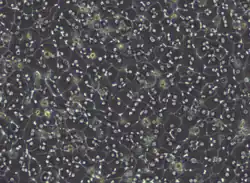

Hepatocytes in cell culture Hepatocytes in cell culture